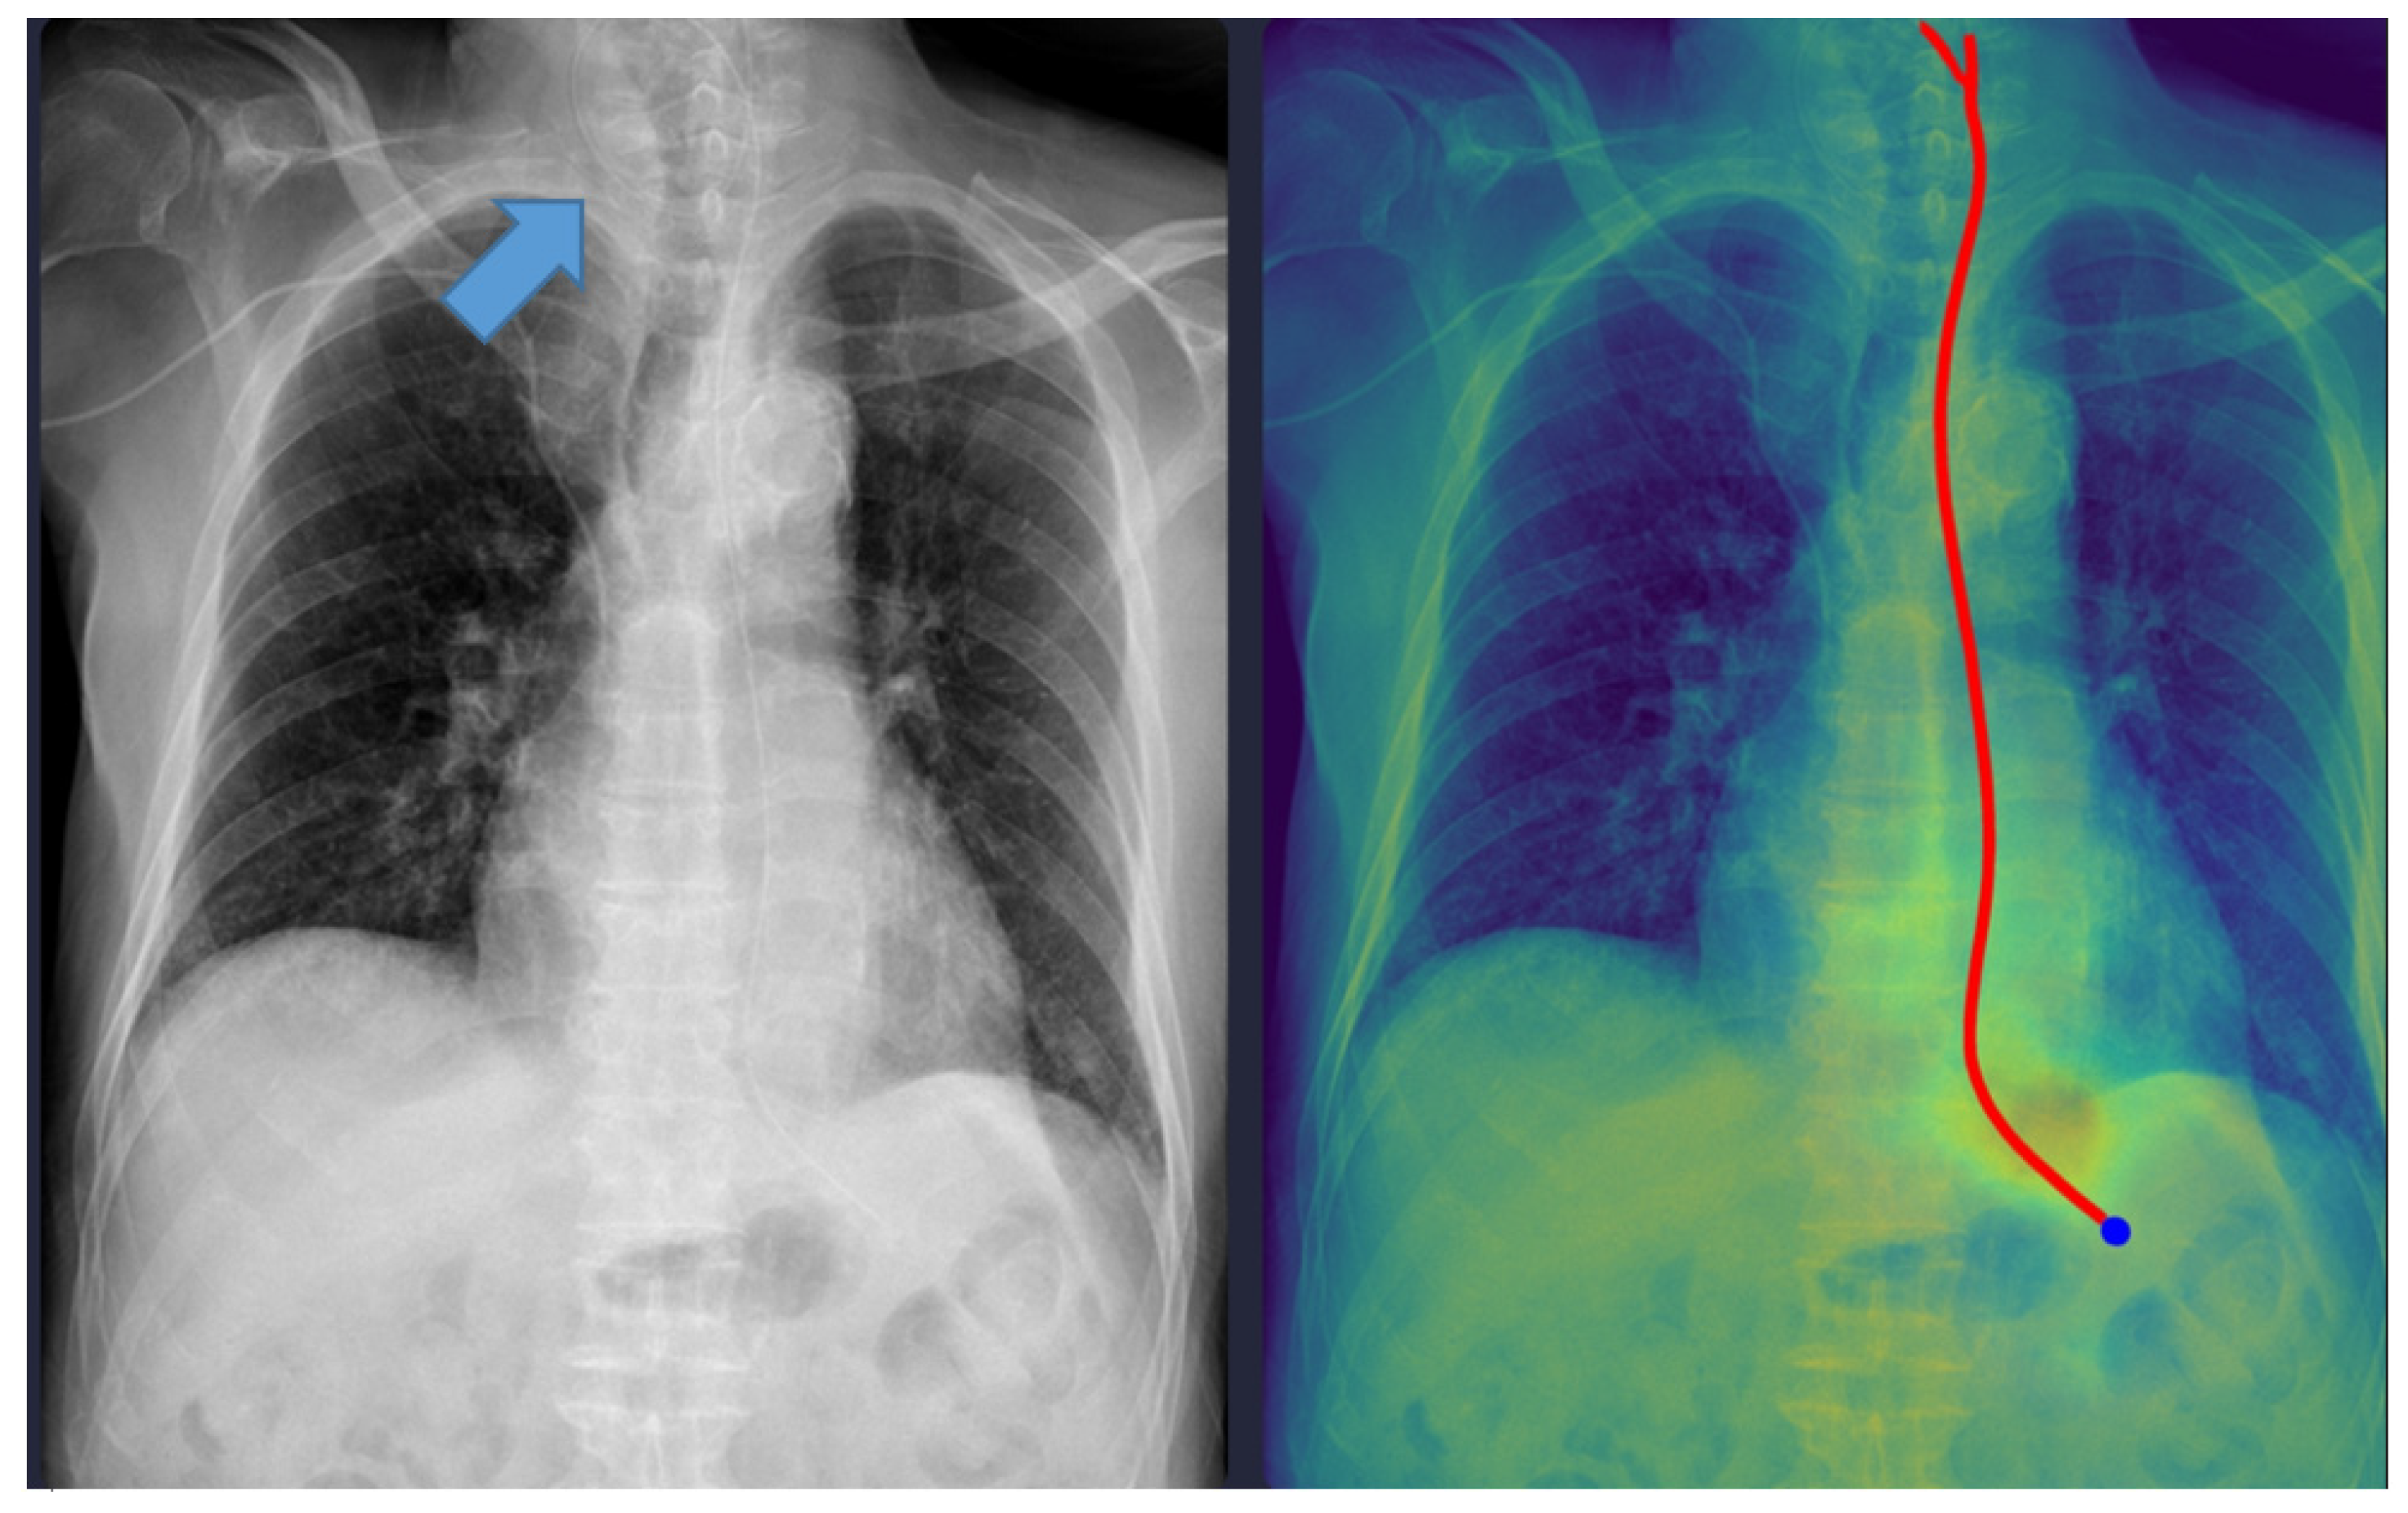

Representative examples of misclassified cases are shown in Figure 2 and Figure 3. The most critical failure involved an NG tube coiled at the indicated site in Figure 2, which suggested incomplete placement and a significant safety risk. The DL model misclassified this case as ‘complete’ based solely on the position of the tip projected below the gastroesophageal junction. Technically, this false-positive classification was highly likely due to the scarcity of such complex, coiled morphological features in the training dataset. While the segmentation module correctly identified the general tube structure, the dual-stage model failed to recognize this pronounced looping or coiling as an immediate risk factor, resulting in the classification module overriding the critical incomplete placement status. This finding identifies a crucial, previously unanticipated failure mode in the model’s design and carries substantial clinical significance, as initiating feeding through a coiled tube presents a high risk of aspiration pneumonia. Moving forward, efforts must focus on incorporating a greater diversity of these rare, yet clinically critical, coiled cases into the dataset to enhance the robustness of the tube segmentation process, thereby ensuring improved and safer clinical implementation. In Figure 3, the DL model failed to draw the entire trajectory of the NG tube and misclassified a complete case as incomplete. A representative example of a correctly classified case is shown in Figure 4. The tip of the NG tube is placed under the gastroesophageal junction and is safe to feed. Because most cases were correctly positioned (=95%), prevalence bias likely inflated the AC1 coefficient, and κ was lower despite near-identical classifications. Future studies should include more incomplete cases to obtain stable reliability estimates [12]. Prevalence-adjusted bias-adjusted kappa (PABAK) estimates were also evaluated with bootstrapping confidence intervals [13]. The results of the agreement among physicians and the DL model are shown in Table 4. Cohen’s κ showed the smallest estimate of 0.644 (95% confidence interval (CI): 0.366–0.922), which increased when using PABAK (0.911 (95% CI: 0.812–0.967)) and Gwet’s AC1 coefficient (0.956 (95% CI: 0.907–0.991)).

Figure 4. Correctly classified nasogastric tube case. The red line represents the trajectory of the nasogastric tube, and the blue dot indicates the tip of the nasogastric tube as identified by the deep learning model.